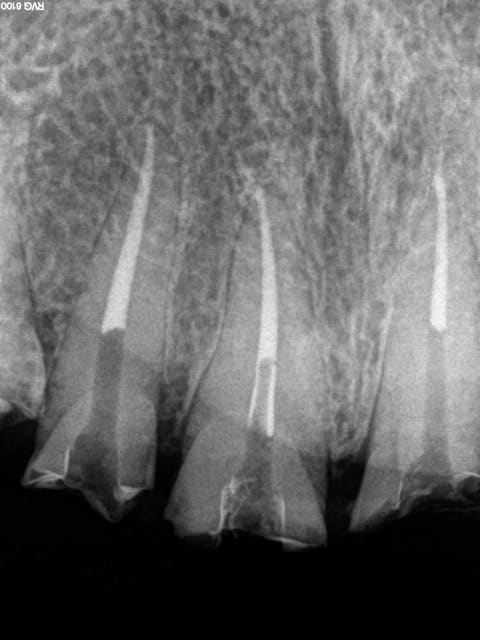

Et 2 autres pour terminer la journée. Ca fait 5 endos molaires aujourd'hui.

Pas trouvé de MV2 sur la 7.